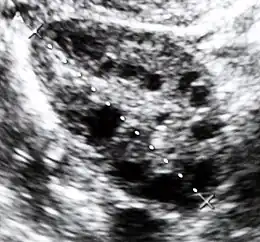

L'échographie pelvienne montre des ovaires augmentés de volume avec un stroma épaissi. La cœlioscopie montre de gros ovaires lisses